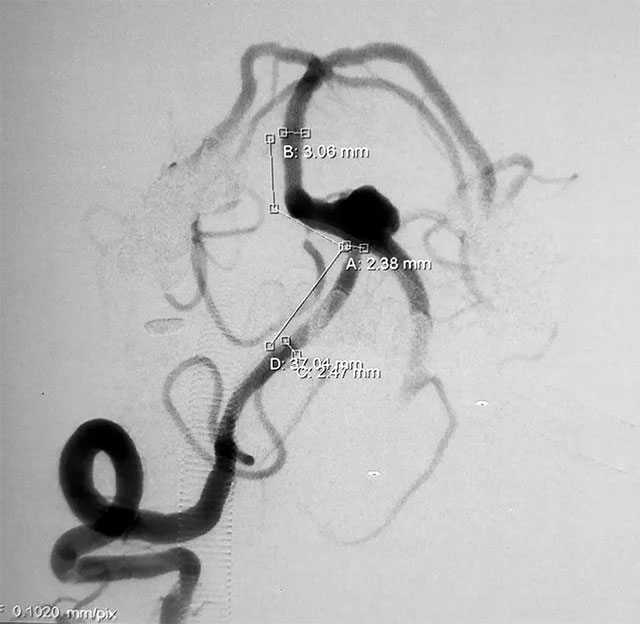

▲ 术前造影

头颅CTA显示:左椎动脉多发狭窄及钙化,呈串珠样改变,椎基底动脉夹层动脉瘤,可见数枚水泡样动脉瘤。患者既往有高血压病史10余年,两月前有“头部外伤史”。血压检查,收缩压153毫米汞柱,舒张压80毫米汞柱,神志清醒,口角右歪。

张琪博士指出,该患者所患颅内夹层动脉瘤影像上属于经典型(I型),且动脉瘤已破裂出现急性蛛网膜下腔出血,导致头晕、头痛、恶心等症状,病情凶险,再出血的风险极大,应及时手术治疗。

并且患者血管条件非常差,DSA造影显示左侧椎动脉远端近基底动脉连接处夹层动脉瘤,伴子瘤,术中很容易破,并且左侧椎动脉闭塞,需要先进性开通,这些无疑增加了手术难度。